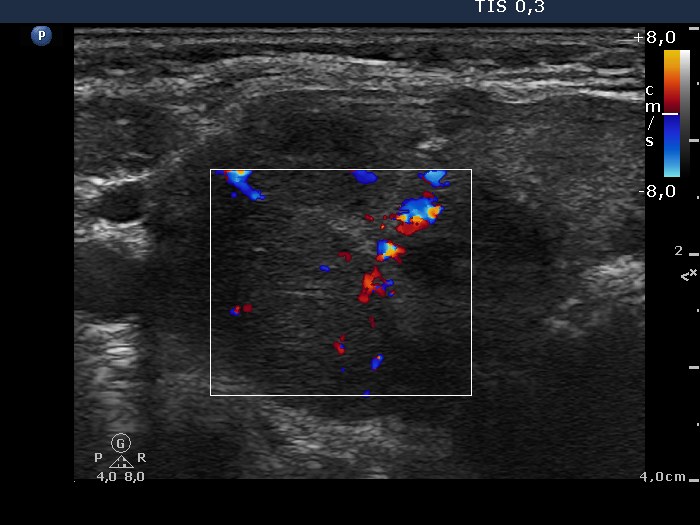

Ultrasonography. There was a large and several smaller, irregular, hypoechogenic lesions in the right lobe. The vascularization was decreased.